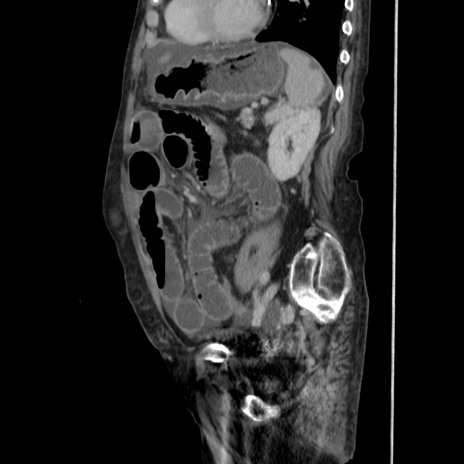

症例31(矢状断像)

【症例】80歳代 女性

【主訴】腹部膨満感

【現病歴】他院にて肝硬変にてフォロー中。1週間前から便秘、腹部膨満感、臍部腫瘤あり受診となる。

【既往歴】肝硬変

【身体所見】腹部膨隆あり、皮膚変化なし、疼痛なし。

【データ】WBC 4600、CRP 0.25